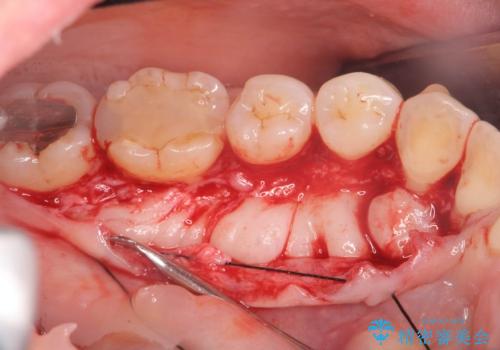

話すのに邪魔な、下顎骨隆起の切除

- 矯正治療を開始するのに伴い、滑舌を含めた改善を計るために、発音の邪魔となる下顎骨隆起の切除を計画します。

手術時間は約30分程度(大きさにより)今回は手術中に、静脈麻酔を行うことで負担なく治療を行う計画としました。